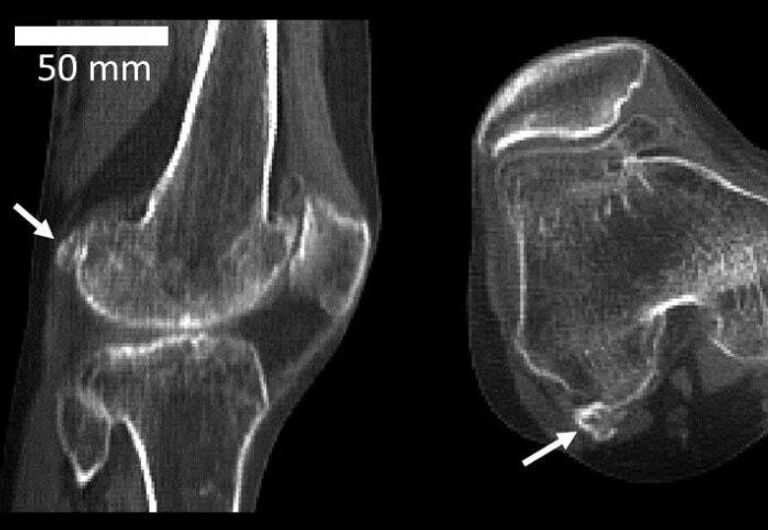

Миллионы лет назад, на заре становления человеческого вида, из колена исчезла за ненадобностью маленькая косточка — флабелла. В последнее время ее снова начали находить.

Флабелла — одна из сесамовидных костей, располагающихся в сухожилиях. У животных она сформировалась примерно двести миллионов лет назад, чтобы придать прочности суставам, защитить сухожилие от повреждения при сильных нагрузках. Считается, что у человека эта кость повышает механическое сопротивление икроножной мышцы. Но зачем это нужно?

Обычно флабелла появляется в обеих коленях и служит причиной осложнений после хирургических операций по замене суставов. В имплантате ее присутствие не учитывают, и это вызывает боль при ходьбе. В итоге "лишнюю" кость приходится удалять.

Замечено также, что у людей с флабеллой нередко встречаются некоторые нейропатические заболевания, а риск остеоартрита колена увеличивается в два раза. Но что причина, а что следствие, пока неясно.

Флаббела — крошечная кость в колене — стала появляться у людей все чаще за последние 150 лет